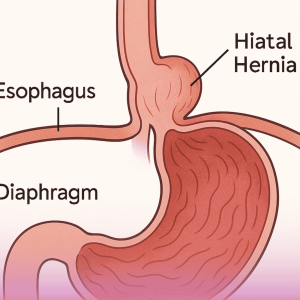

جراحة إصلاح الفتق الحجابي

الفتق الحجابي هو حالة تحدث عندما يندفع جزء من المعدة إلى التجويف الصدري عبر فتحة غير طبيعية أو متسعة في الحجاب الحاجز، وهو العضلة التي تفصل بين الصدر والبطن. غالبًا ما يكون الفتق الحجابي مصحوبًا بأعراض الارتجاع المعدي المريئي.